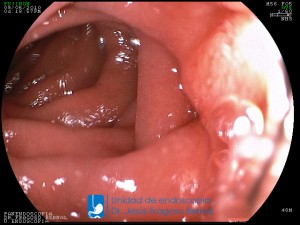

La Unidad de Endoscopía fue creada en 2002 por el Dr. Jesús Fragoso Bernal, es pionera en el estado por la utilización de la tecnología más avanzada, que nos permite ofrecer servicios integrales de diagnóstico y tratamiento para las enfermedades del aparato digestivo.

"La Unidad de Endoscopía se ha caracterizado por un progreso continuo desde su inicio marcando la pauta en los procedimientos endoscópicos en el estado de Tlaxcala y estando siempre a la vanguardia tecnológica."

Dr. Jesús Fragoso Bernal